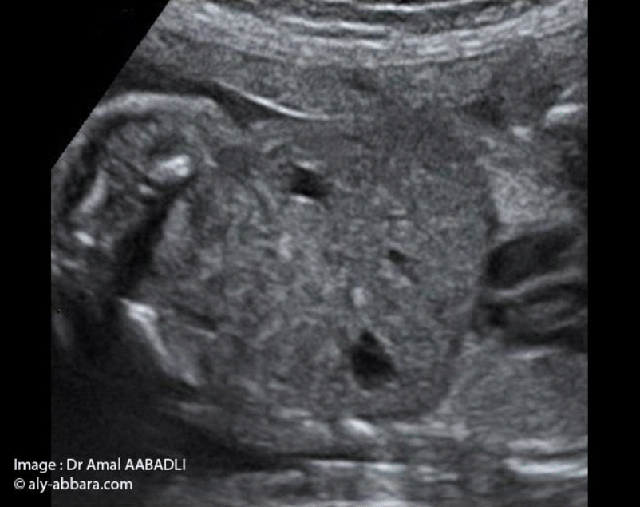

من بين الصور الضرورية و الأولية لفحص الجنين توجد صورة الحجاب الحاجز التي تظهر القلب و الرئة من جهة و المعدة من جهة ثانية و يفصل بينهم الحجاب الحاجز.

هذه الصورة مهمة جداً لنفي حالات فتف الحجاب الحاجز و لا يمكن أن يتم فحص الجنين في الثلاثية الثانية من الحمل دون تدوين هذه الصورة شأنها شأن صور الرأس و البطن

هذه الصورة سهلة المنال و يحصل عليها بقطعة طولية سهمية للجنين مائلة إلى اليسار حيث توجد المعدة.

• Parmi les images nécessaires lors de la réalisation d'une exploration échographique fœtale, c'est l'image sur laquelle on met en évidence le cœur et le poumon d'un côté, puis l'estomac de l'autre côté, avec le diaphragme séparant ces deux côtés de l'image.

• Il s'agit d'une image nécessaire permettant d'éliminer la présence d'une hernie diaphragmatique ; il ne faut pas qu'une exploration échographique fœtale soit réalisée au cours du deuxième trimestre de la grossesse, sans produire cette image comme c'est le cas pour la coupe de la tête et le ventre fœtaux.

• Cette icône échographique est facile à obtenir en réalisant une coupe sagittale sur le tronc fœtal déviée vers la gauche.